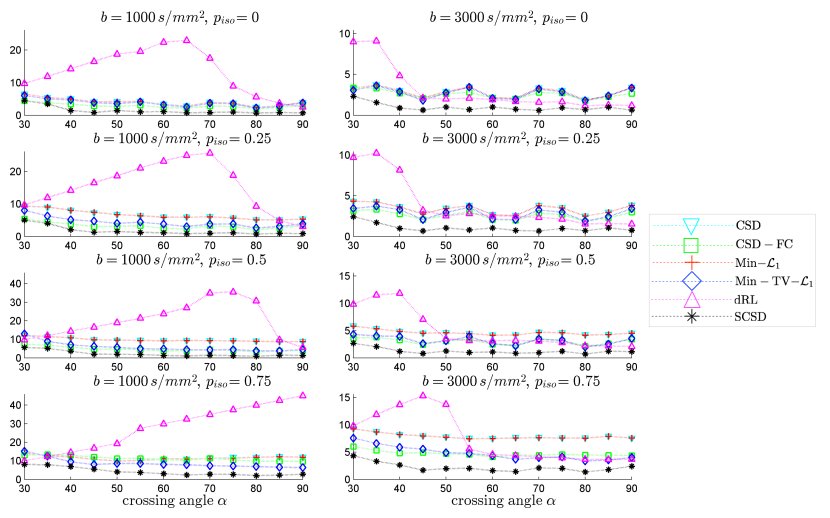

The left and right columns of subplots in Fig. 4 show the values of AAE as a function of crossing angle , which have been obtained with the proposed and reference methods for s/mm2 and s/mm2, respectively. The regularization parameters for Min-, CSD-FC, Min-TV-, and SCSD were set to optimize the overall performance of the algorithms, namely: 1) for Min-, 2) for CSD-FC, 3) , for Min-TV-, and 4) , , for SCSD. The dRL method has been reproduced following its description in [44]. One can see that all the error curves, with the exception of that of dRL, exhibit the expected behaviour where AAE decreases with an increase in . Moreover, despite the substantially worse noise conditions for s/mm2, all the tested methods (again, with the exception of dRL) demonstrate better performance for s/mm2, as compared to the case of s/mm2. In all the cases, however, the proposed SCSD method shows considerably better performance in comparison to the alternative solutions, with the “second best” results produced by CSD-FC for lower values of and by Min-TV- for higher values of .

Before proceeding any further, one additional comment is in order regarding the behaviour of the AAE curves obtained with dRL. Specifically, one can see that, for s/mm2, the AAE is minimized for smaller values of , which is rather a counter-intuitive result. To understand why this happens, it is instructive to examine the behaviour of the TP curves produced by dRL (see Fig. 5). Specifically, one can see that for s/mm2 and , dRL is incapable of resolving the crossing fibres of the numerical phantom for , with the resolvability problem becoming progressively worse with an increase in . In this case, the values of AAE effectively “mirror” those of up to the point when dRL starts detecting the correct number of fibres, after which AAE becomes a decreasing function of the fibre crossing angle. It also deserves noting that for s/mm2, dRL demonstrates considerably improved performance in terms of AAE, even surpassing CSD and Min- for and . However, in all the alternative scenarios, the performance of dRL remains inferior to that of other methods under comparison. A possible explanation to this fact could be that the Lucy-Richardson algorithm exploited by dRL aims at recovering a maximum likelihood estimate under the assumption on measurement noise to be Poissonian. However, such a noise model can hardly be a good approximation to Rician distribution, which is inherent in MRI.